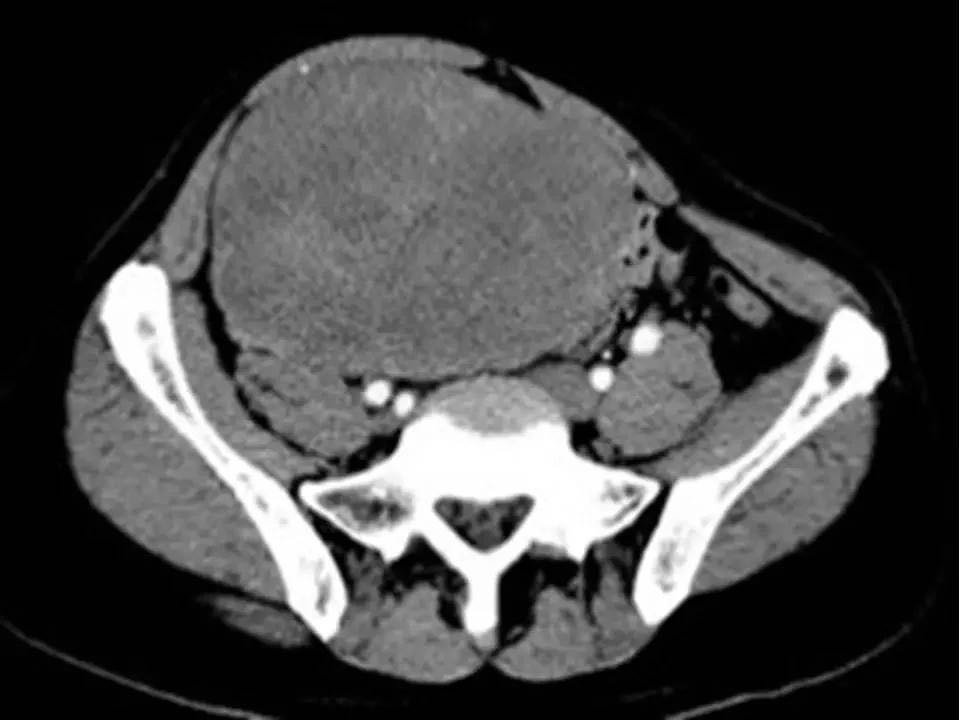

MRI表现,腹盆腔见不均质肿块,与肌肉相比为等低密度,强化不明显。T1WI信号均匀,T2WI高低混杂信号,增强后渐进性强化,病变各序列可见斑片状低信号区。 诊断,腹腔侵袭性纤维瘤病。

AF的影像学表现具有一定特征性。影像上表现为边界欠清的软组织肿块,钙化、出血少见,即便在较大的肿瘤中也看不到中央性坏死。病灶CT密度欠均匀,与邻近骨骼肌相近,强化不明显。T1WI信号基本均匀,明显或中度强化,典型强化方式呈渐进性。所有序列中都可以看到一定的低信号区,在病理上相对应的为病变内胶原纤维丰富的区域,此区域强化较轻。 侵袭性纤维瘤病虽然少见,但是平常工作中需要考虑到侵袭性纤维瘤病的诊断,尤其是中年女性腹腔的肿块。MRI为最佳的检查方法,可以显示一定的影像学特征。